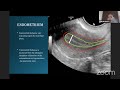

Basic Ultrasound & It's Clinical Implications In F...